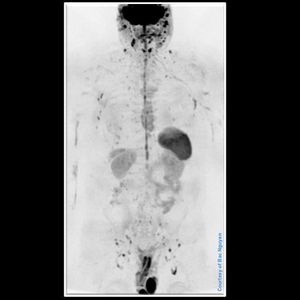

Whole Body Diffusion Weighted Imaging (WBDWI)

Whole Body Diffusion Weighted Imaging (WBDWI) – direct coronal acquisition @ Siemens 1.5T Sola WBDWI acquired in direct coronal from a MAGNETOM Sola 1.5T system. Multiple stations acquired with b50, b1000 and ADC map in less than 6min.